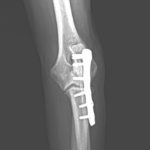

尺骨近位端肘頭骨折

尺骨の近位端の肘頭骨折をしているワンコがいるので手術で対応して欲しいと連絡がありました。高いところからジャンプして着地に失敗してしまったとの事です。さて、この部分の骨折は上腕三頭筋の牽引力に抵抗するための強固な固定が必要です。橈骨遠位端用の1.5 mm Titanium T-typeLocking Plateで接合術を行います。手術をする事で、早々に肘の曲げ伸ばし運動などのリハビリテーションを実施する事が可能となり、後遺症の発生を少なくする事を目的としています。